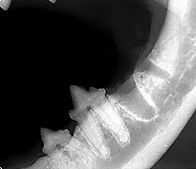

Lesão de

Reabsorção Dentária

Também conhecida como lesão absortiva odontoclástica felina, é uma doença caracterizada por lesões erosivas do esmalte ou cemento, frequentemente situada na porção cervical do dente e classificada de acordo com origem e grau de acometimento, desde lesões superficiais em cemento e dentina, até a exposição pulpar e destruição completa da coroa dentária.